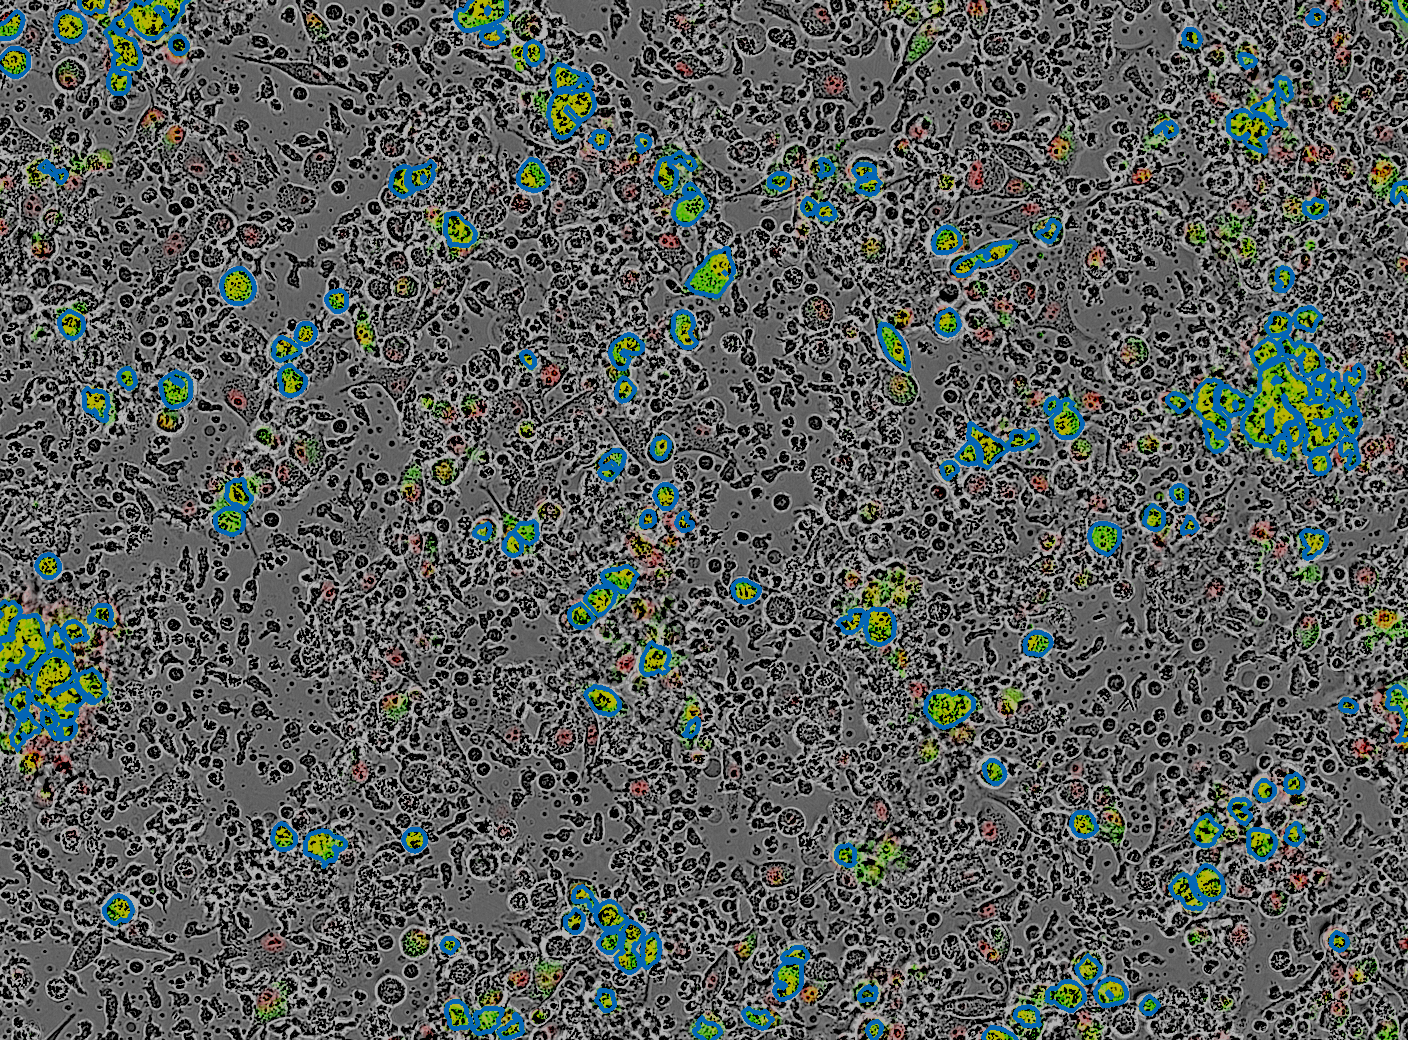

T cell Synthetic Workflow for Immune Function Testing

We created a streamlined pipeline that reprograms T cells using synthetic mRNA, allowing for a high-throughput screening method that accelerates TCR discovery into a faster and more scalable process for developing next-generation therapies.